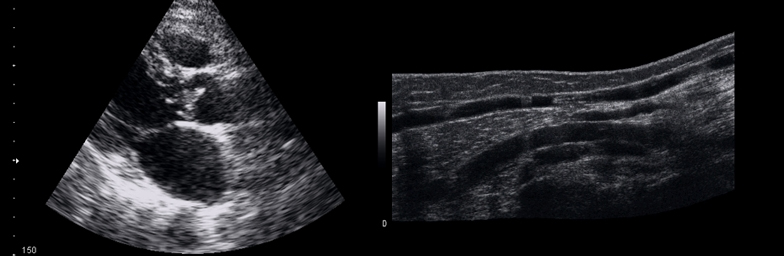

Explorarea ecografică este o examinare exactă prin care se pot detecta și diagnostica din timp o serie de afecțiuni asimptomatice. Examinarea este nedureroasă, nu are contraindicații și se poate efectua preventiv sau când este necesar pe parcursul evoluției unei boli.